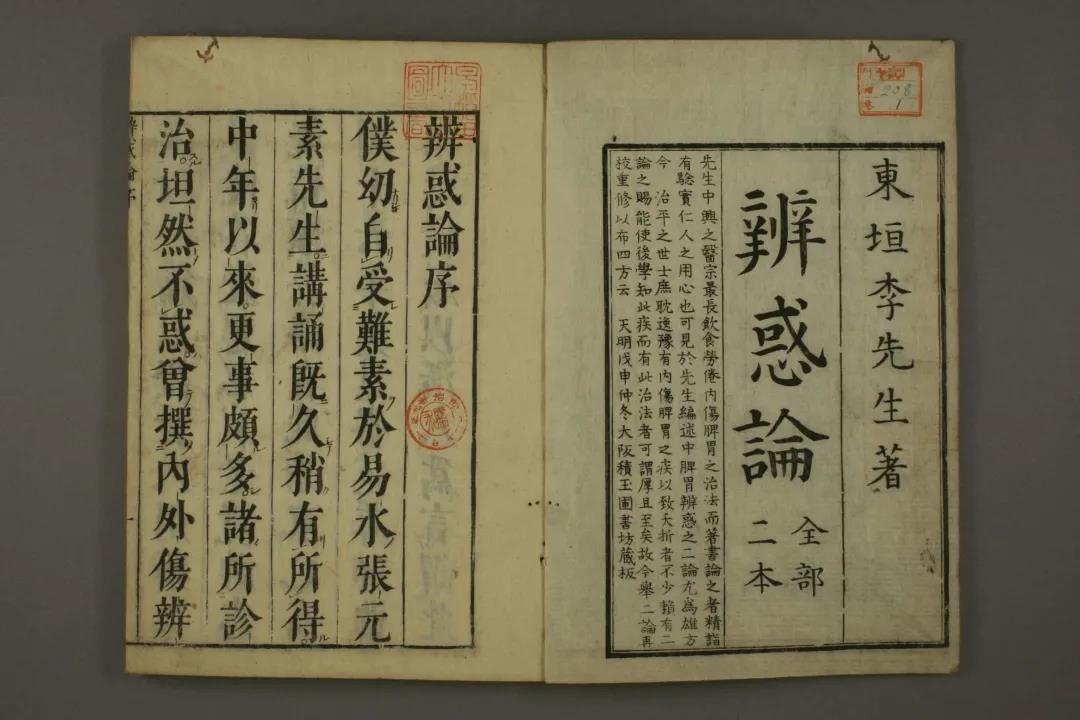

中医古籍癌症系列之肺积|肺癌

中医古籍癌症系列之肺积|肺癌

中医古籍癌症系列之肺积|肺癌

中医古籍癌症系列之肺积|肺癌